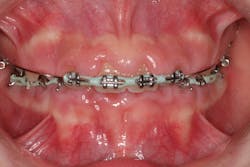

Medication-induced (drug-induced) gingival enlargement can be caused by certain classes of drugs people may be taking.1 The following classes of drugs have been associated with gum overgrowth:

- Anticonvulsants (phenytoin, phenobarbital, lamotrigine, vigabatrin, ethosuximide, topiramate, and primidone)

- 50% of the cases are typically attributed to phenytoin (figure 3).